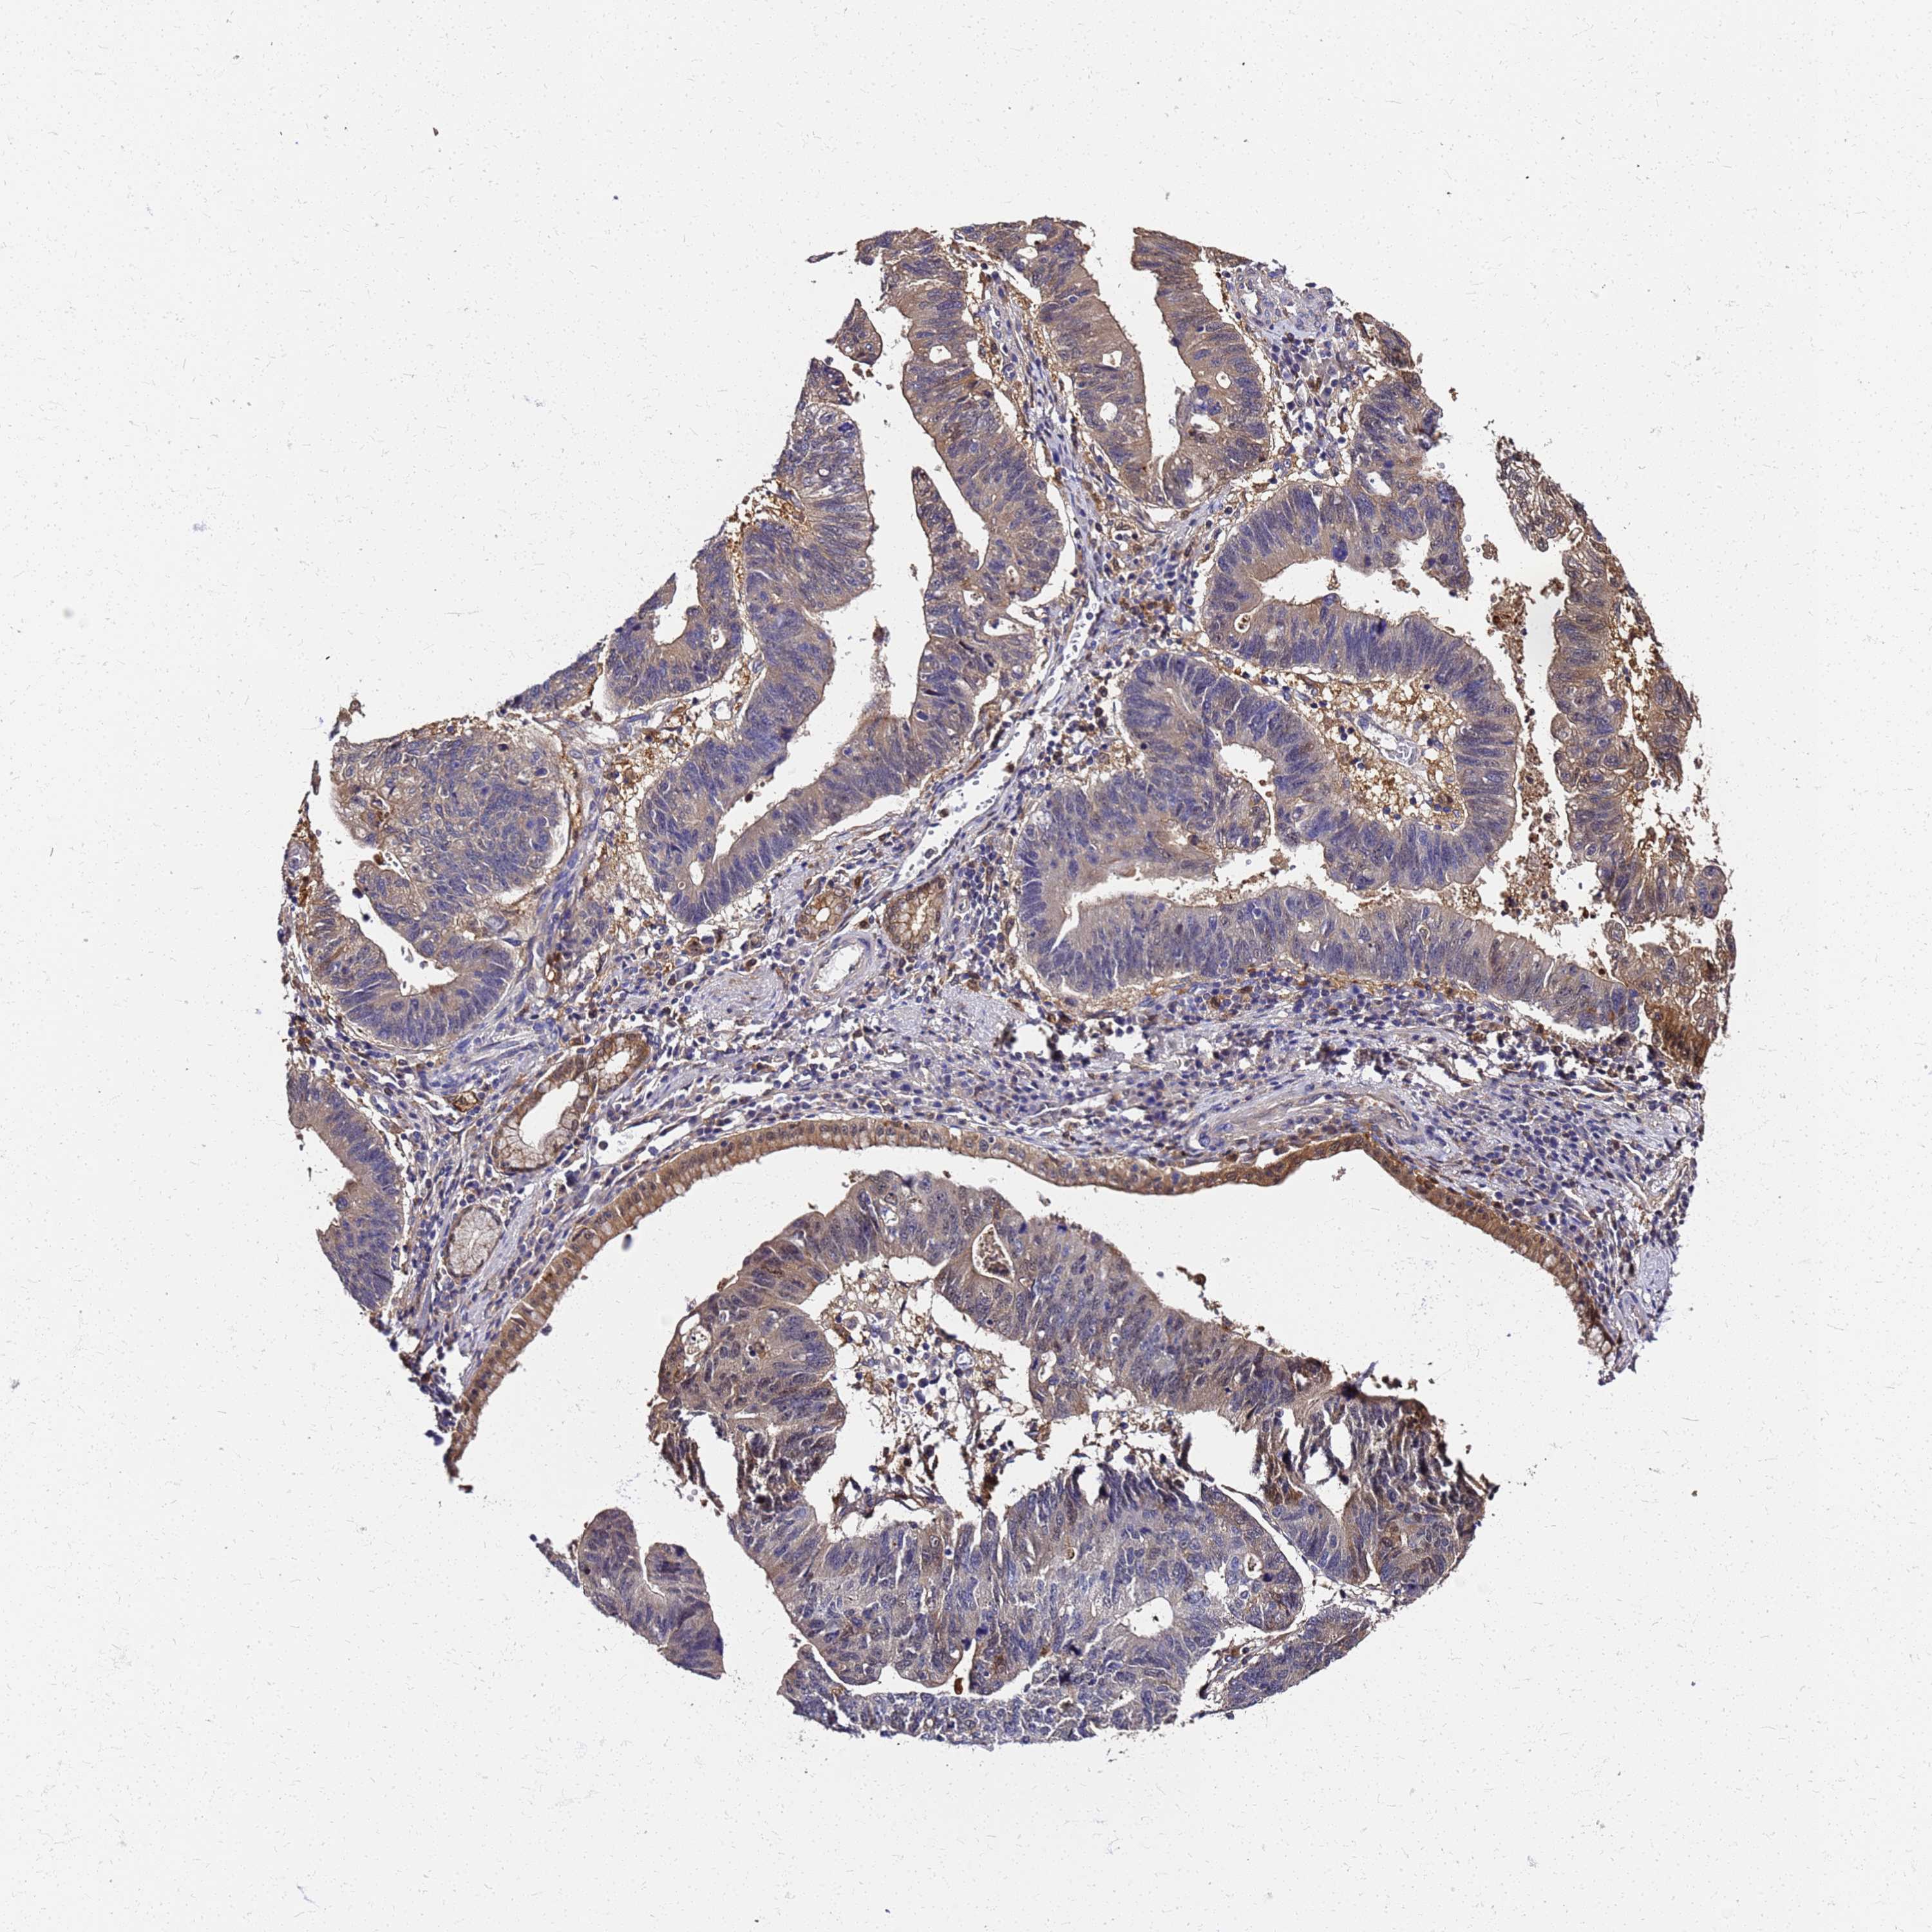

STOMACH CANCER - Protein expressioni

A mouse-over function shows sample information and annotation data. Click on an image to view it in a full screen mode. Samples can be filtered based on level of antibody staining by selecting one or several of the following categories: high, medium, low and not detected. The assay and annotation is described here.

Note that samples used for immunohistochemistry by the Human Protein Atlas do not correspond to samples in the TCGA dataset.

Antibody stainingi

Antibody staining in the annotated cell types in the current human tissue is reported as not detected, low, medium, or high, based on conventional immunohistochemistry profiling in selected tissues. This score is based on the combination of the staining intensity and fraction of stained cells.

Each image is clickable and will lead to virtual microscopy that enables deeper exploration of all samples and also displays staining intensity scores, fraction scores and subcellular localization as well as patient and tissue information for each sample.

Antibody HPA042745

Antibody CAB034320

Staining

High

Medium

Low

Not detected

Intensity

Strong

Moderate

Weak

Negative

Quantity

>75%

75%-25%

<25%

None

Location

Nuclear

Cytoplasmic/membranous

Cytoplasmic/membranous,nuclear

Adenocarcinoma, NOS